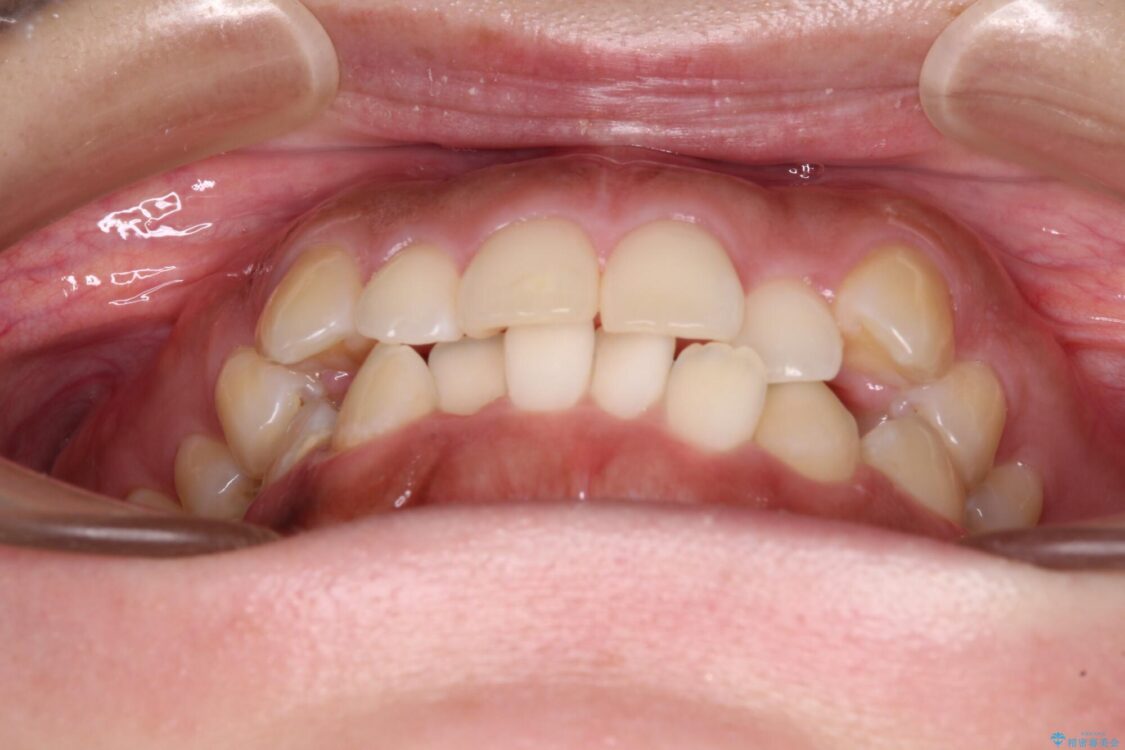

前歯の叢生と八重歯を気にして来院された患者様です。

治療前

• 【モニター】カリエール・ディスタライザーを併用した八重歯のインビザライン矯正 治療前画像